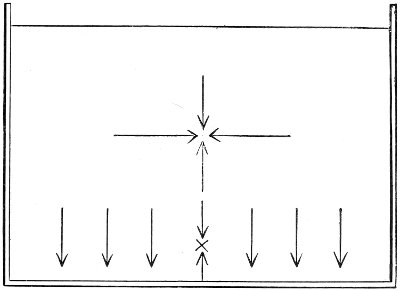

Fig. 22.—Sagittal section showing relations of the several layers of fascia within the pelvic floor (Dickinson).

The vagina extends, as a transverse slit in the pelvic floor, upward and backward, approximately in the direction 60 of a line drawn from the ostium vaginæ to the fifth sacral vertebra. It is approximately parallel with the conjugate of the brim, so that when the woman is erect the long axis of the vagina is inclined at an angle of 60° to the horizon. The vagina is not a vertical open tube: it is a slit in the pelvic floor, in health always closed by the accurate apposition of the anterior and posterior walls (Fig. 21). The anterior vaginal wall is about 2½ inches long in a vertical mesial line. The posterior vaginal wall is about 3½ inches long. The vaginal walls are triangular in shape, being broader above than below. The shape of the normal vagina at the pelvic outlet is shown by Fig. 23. The section here shows the vaginal 61 slit of the shape of the letter H. The portions of the slit extending backward and somewhat outward are called the vaginal sulci or furrows. They are directions of diminished resistance in which tears are liable to occur.

The vagina passes through these structures. They surround and support the ostium vaginæ as the fascia and muscles surround and support the opening of the rectum or the anus. The muscles and fasciæ are attached in the median line between the anus and the vagina, and therefore this part of the body, which is called the perineum, is supported or maintained in its 58 proper position by these various structures. The transversus perinæi arises from the ramus of the ischium and is inserted in the perineum. The bulbo-cavernosus, or sphincter vaginæ, arises in the perineum and is inserted in and about the clitoris. The inner fibers of the levator ani arise from the symphysis pubis and are inserted in the perineum and the lower part of the vagina (Fig. 20). When these muscles contract, their action, therefore, is to draw the perineum upward and forward. At the same time the anus is drawn upward and forward, and so also is the posterior margin of the ostium vaginæ and the lower portion of the posterior vaginal wall.

The vagina has no circular sphincter like the anus, but 59 the vaginal month is kept closed by the action of the transversus perinæi, sphincter vaginæ, and levator ani muscles, which draw the perineum forward, and thus keep the posterior vaginal wall in apposition with the anterior wall.